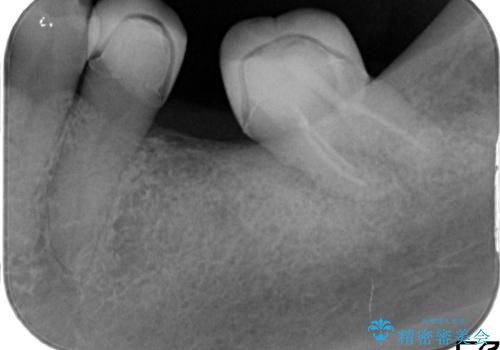

左下6を抜いてからブリッジを入れるまでに放置してしまったために、左下7が前に倒れたこと、左下8も後ろから押す向きに生えていたこともあり、左下7がかぶせものを入れづらい状態になっていたためと考えられました。

また左下7は倒れていたため、清掃性が悪く近心のポケットは7mmありました。